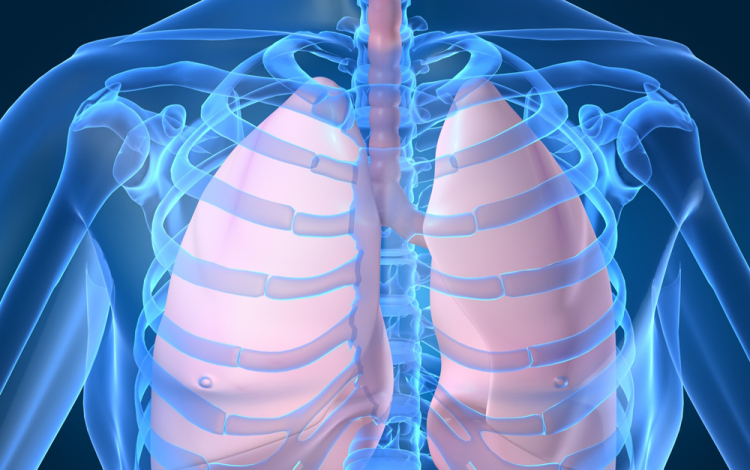

Húszan várnak tüdőátültetésre Magyarországon

Húszan várnak tüdő-transzplantációra az országban, tavaly 12 magyar betegen hajtottak végre ilyen szervátültetést külföldön

- mondta Kásler Miklós, az Országos Onkológiai Intézet főigazgatója vasárnap az M1 aktuális csatorna esti műsorában. A főigazgató ezt azzal kapcsolatban közölte, hogy még idén elvégezhetik az első tüdőátültetést Magyarországon.

Magyarországról tavaly 37 tüdőt szállítottak Bécsbe átültetési céllal; ha nálunk is elérhetővé válik a műtét, akkor várhatóan a környező országokból is Budapestre érkezik majd a betegek egy része Bécs helyett - mondta a főigazgató.